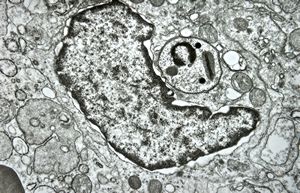

poxvirus - molluscum contagiosum